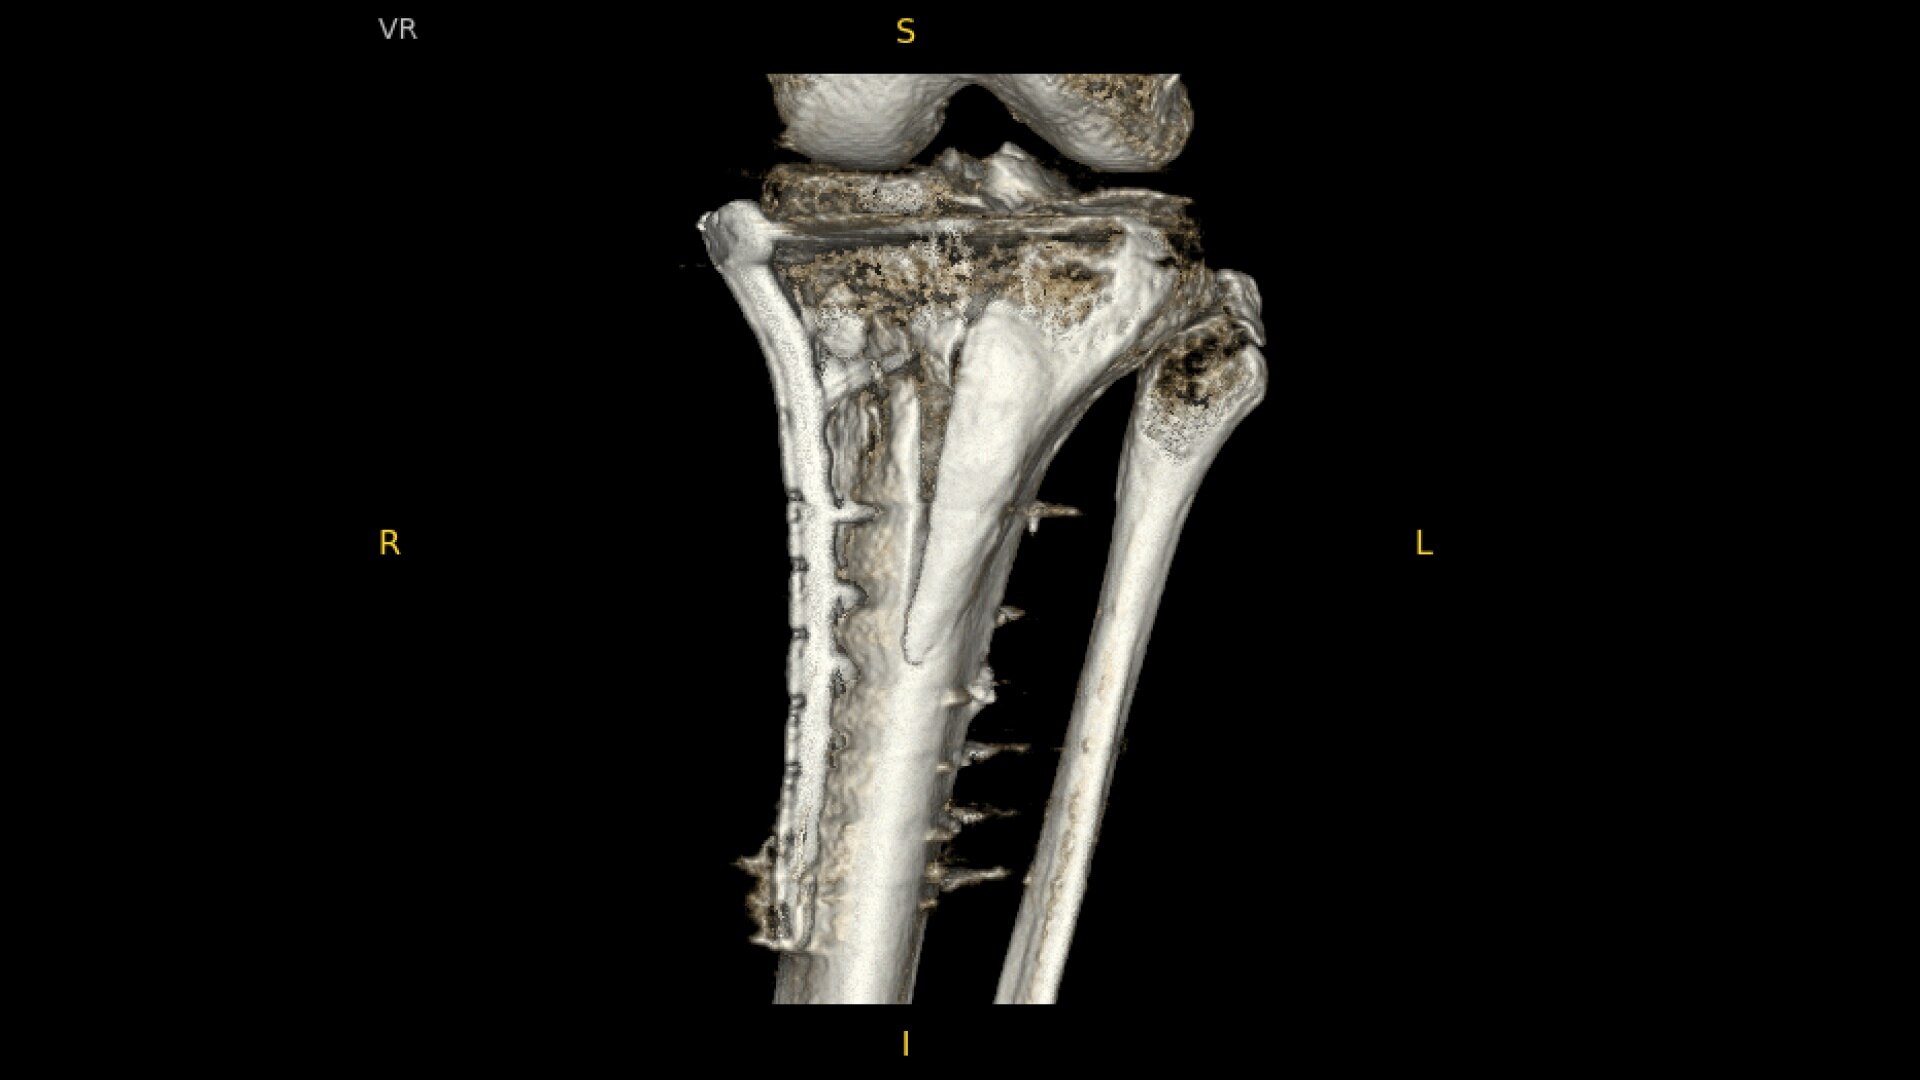

OEC C-arms provide orthopedic imaging with a large field of view optimized to clearly visualize orthopedic anatomy, such as the entire long bone femur or minute fractures in extremities. A clear display with comfortable viewing can easily show AP and lateral views, enabling efficient procedure planning.

See precise anatomical detail of varying densities such as bone and soft tissue with a high dynamic range with the OEC Elite CFD with a flat detector, image processing advancements and 4K viewing display.

Complex orthopedic procedures require powerful imaging systems. OEC premium C-arms perform in a variety of procedures such as:

• Pilon fracture fixation